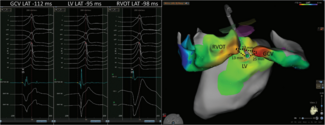

Ibragim Al-Seykal, MD; Tobias Ahnert; Ankit Maheshwari, MD

Ibragim Al-Seykal, MD, and colleagues describe a case of successful left ventricular summit premature ventricular complex ablation.